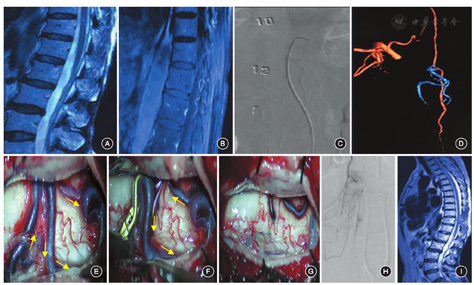

患者女,64岁。因"左侧臀部、下肢疼痛及麻木1年,加重伴行走困难1个月"入院。自诉疼痛呈"放电样",在触摸左侧大腿内侧时可引发疼痛,活动或劳累后加重,持续数分钟,休息后可自行缓解,无肢体乏力、括约肌功能障碍等症状。外院曾诊断为"腰椎间盘突出",给予对症治疗和理疗后效果差。患者1个月前疼痛症状加重,不能行走。入院查体:四肢肌力、肌张力正常,深、浅反射和感觉正常,括约肌功能正常。肌电图检查未见明显异常。行腰椎MRI检查(图1A,图1B):T2加权成像上T11水平可见点灶样高信号,脊髓水肿不明显,未见明显的流空信号;强化后可见相同部位有增粗的血管影,部分位于髓内或位于脊髓背侧面,其节段局限,远端向下走行,向椎管外引流。脊髓血管造影检查(图1C,图1D):左侧T10肋间动脉发出前根髓动脉后,在T8下缘水平加入脊髓前动脉,其向下走行至T11水平发出穿动脉并形成瘘口。瘘口以远为静脉穿行于脊髓内并从脊髓背侧穿出,在脊髓背侧表面异常增粗成袢,向下、外侧走行,于左侧L1水平经硬膜穿出椎管。注入对比剂后,静脉在11 s时才开始显影,明显晚于常见的动静脉瘘造影时静脉显影的时间。手术于复合手术室实施,首先在左侧股动脉置入长鞘,无菌敷料保护穿刺点,患者取俯卧位,行后正中入路神经根减压术。术中打开硬脊膜后,可见脊髓背侧异常增粗的引流静脉(图1E~G),在神经根起始处穿行并卡压神经根,神经根表面的血管迂曲扩张,呈现"串珠样"改变。术中造影发现静脉显影时间比术前造影明显延迟,注入对比剂后至22 s引流静脉才缓慢显影,考虑为术中采用俯卧位、腹腔压力增高、静脉高压逆向传导至根静脉所致。同时,术中美兰造影确认责任血管无误后(图1H),将此迂曲扩张的静脉电灼并切除,从而达到神经根减压的效果。由于术中对位于腹侧的髓周动静脉瘘显露困难,故未予进一步处理。术后第1天患者主诉疼痛消失,无新增神经功能障碍。复查腰椎CT可见部分残留的静脉显影。术后3个月复查腰椎MRI,脊髓未见明显异常(图1I),出院后6个月随访患者未再出现神经根疼痛症状,且无新增神经功能障碍。

Takai[1]根据瘘口的大小、供血动脉的数量、静脉高压的程度,将脊髓髓周动静脉瘘分为3个亚型:A型,小瘘口,单支供血动脉,静脉扩张不明显,低流量;B型,中等瘘口,多支供血动脉,引流静脉扩张明显,中等流量;C型,大瘘口,多支供血动脉,引流静脉扩张迂曲,呈静脉球样改变,高流量。通常,本病的临床表现为步态异常、感觉异常、括约肌功能障碍等,且缓慢进展[2]。MRI表现为脊髓表面流空信号伴有脊髓水肿。静脉高压、血流瘀滞和脊髓缺血是本病的病理基础。本例脊髓髓周动静脉瘘属于A型,其瘘口小、流量低,由单支细小动脉供血。MRI上流空效应不明显,仅可见局部强化的异常血管影,其可能与流量小、流速低有关。同时无脊髓水肿表现,且无脊髓功能障碍,说明脊髓静脉压力并不高。术中发现1根粗大的根静脉异常扩张,并卡压神经根,同时可见神经根表面的血管因受卡压也呈现"串珠样"改变,是导致神经根疼痛的原因。其致病机制类似于三叉神经痛、面肌痉挛时神经与血管的关系,术中通过血管减压可达到较好的临床效果。